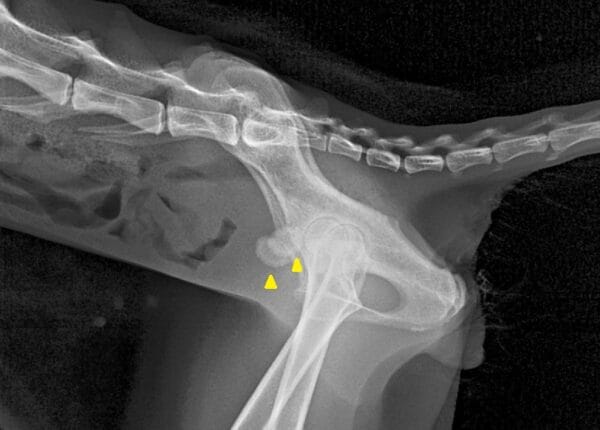

◆ 難しいケース

・小さな石が無数に存在。数も形も多様で摘出が困難である

・レントゲン撮影を何度も繰り返し、残存石のチェックが必要である

・骨盤の骨と陰影が重なり、画像検査での完全な描出が困難になることもある